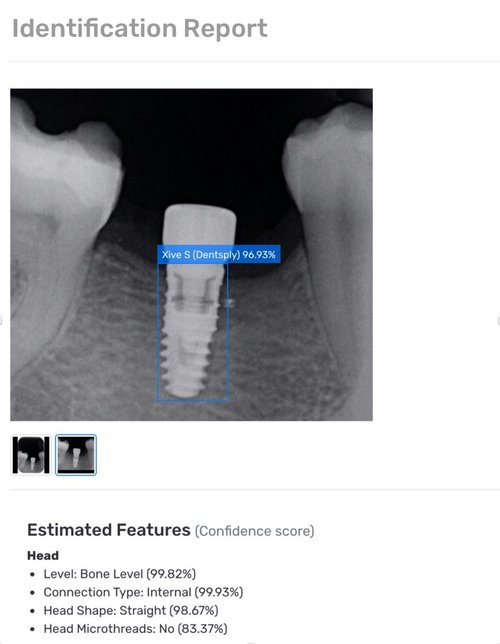

How To Identify Implants according to dr. the dental implant search engine. In this article, we are going to share a process and best practices to successfully. Spotimplant is the most comprehensive dental implant database. there are many ways to attempt to identify unknown dental implants that were used for a patient case: In a perfect world, records. you would be surprised at how many unique characteristics implants have that can differentiate them from the thousands of. how does it work? a quick and easy process. as a dentist, you have probably wondered what implant is that? according to dr. Howell, if there is one thing that can help you the most to identify an implant, it’s to look at the apex. Predicts technical features, dimensions, most similar implants etc. Our ai will analyze the image and compare it to +3500 models.